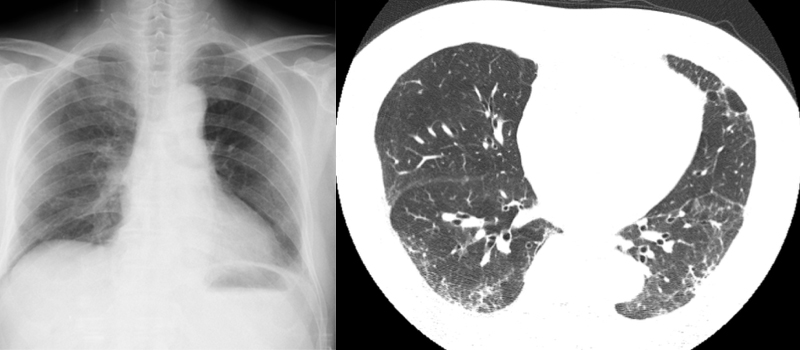

(9) 폐섬유증

폐섬유증은 폐조직에 섬유화가 발생하여 폐의 기능을 저하시키는 질병으로, 호흡 곤란, 기침 가래 등의 증상이 나타납니다. 이 질환은 환경적, 유전적, 방사선 노출 등 다양한 원인이 있습니다.